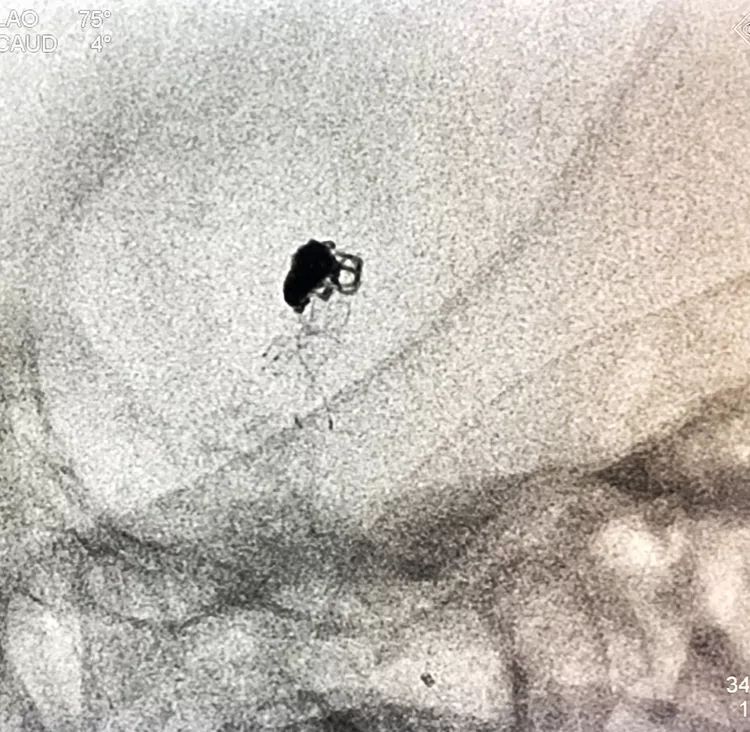

将LVIS支架(3.5×15)跨瘤颈释放于右侧PCA-基底动脉内

在支架保护下输送弹簧圈栓塞瘤腔

此时从工作位(右斜17°反汤9°)看弹簧圈分布致密,微导管头已被顶到瘤颈处